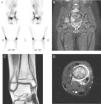

A) Gammagrafía con 99Tc: aumento de captación en acetábulo derecho y en la cortical medial de la tibia derecha en su parte distal. B) RM lumbosacra y caderas: afectación de pilar posterior del acetábulo derecho con extensión a pala iliaca derecha de predominio medular. Afectación del cuerpo de S1 sin lesión perióstica ni afectación del disco. C) y D) RM tobillo derecho: afectación de la metáfisis distal de la tibia derecha con extensión epifisaria con lesión lítica y edema perilesional con afectación perióstica en capas de cebolla.

Niña de 10 años, sana, que ingresa por 15 días de febrícula, pérdida de peso, mialgia, dolor en tobillo derecho y lumbalgia. Exploración: leve tumefacción en maléolo interno de tobillo derecho, dolor intenso a la bipedestación y deambulación. Pruebas complementarias: hemograma normal, PCR 18mg/l, VSG 45mm/h, Mantoux 0mm, radiografía lumbosacra y ecografía abdominal normales, y radiografía de tobillo derecho con lesión lítica en cara interna y levantamiento perióstico. Ante la sospecha de osteomielitis aguda, se inicia tratamiento con cefotaxima y cloxacilina por vía intravenosas. Dada la presencia de focos dolorosos sin expresión radiográfica, se realiza una gammagrafía ósea, que revela hipercaptación en acetábulo y metáfisis distal de tibia derechos. La resonancia magnética objetiva un tercer foco osteolítico en cuerpo de S1 (fig. 1). Tras 5 días de tratamiento, presenta empeoramiento del estado general, persistencia de la fiebre y elevación de PCR (415mg/l) y VSG (110mm/h), apareciendo nuevo foco doloroso malar derecho, por lo que se sustituye cloxacilina por vancomicina ante la sospecha de S. aureus resistente a meticilina adquirido en la comunidad. Debido a la evolución tórpida, se decide biopsia ósea al 12.° día de ingreso, que muestra inflamación crónica y fibrosis. Todos los cultivos obtenidos de sangre y hueso, incluidos hongos y micobacterias, fueron negativos. La evolución posterior es favorable, quedando afebril al 9.° día y con disminución del dolor, por lo que es dada de alta tras 21 días de tratamiento por vía intravenosa para continuar con clindamicina por vía oral. A las 3 semanas del alta, y pese a buena adherencia y descenso progresivo de reactantes de fase aguda (VSG 23mm/h), aparece nuevo foco en la región distal de la tibia izquierda. Con la sospecha de OCMR, se suspende la clindamicina y se pautan AINE durante 1 mes y posteriormente prednisona (0,5mg/kg/d) 2 meses, sin respuesta. Ante la persistencia del dolor y los hallazgos radiográficos, se decide tratamiento con pamidronato por vía intravenosa (1mg/kg/día), 3 dosis consecutivas seguidas de una dosis mensual. Tras 6 dosis presenta buena respuesta, con remisión total del dolor, desaparición de las lesiones malar y vertebral, y mejoría del resto sin efectos secundarios hasta la fecha.